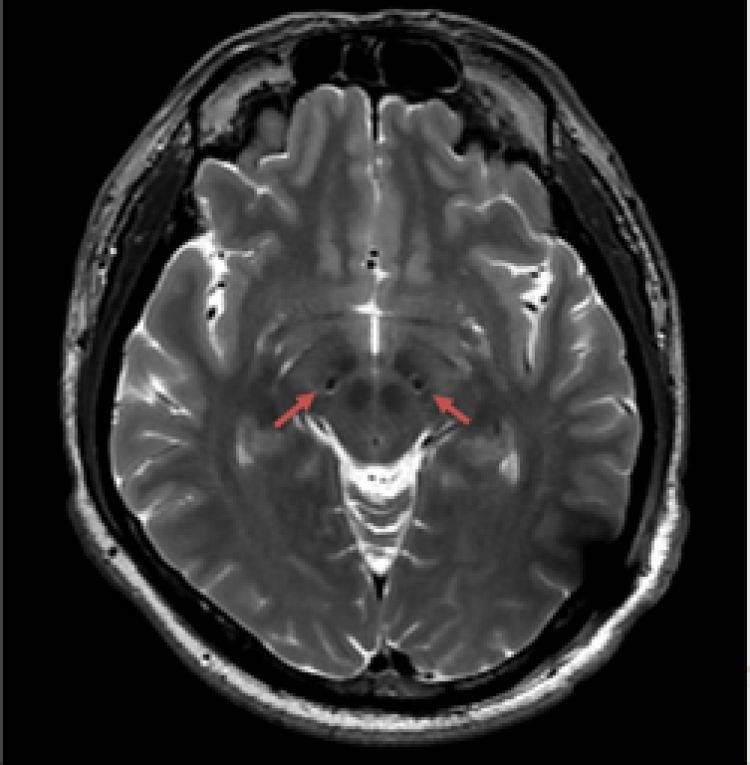

(患者在术后复查3.0T磁共振,提示电极位置精准)